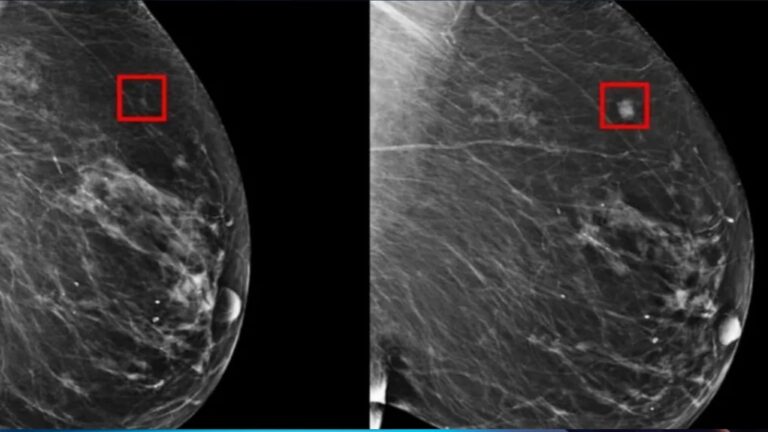

الذكاء الاصطناعي وسرطان الثدي

بريطانيا تعتمد الذكاء الاصطناعي للكشف المبكر عن سرطان الثدي

الذكاء الاصطناعي يكشف عن خطر الإصابة بسرطان الثدي قبل سنوات من التشخيص

دراسة ألمانية تكشف دور الذكاء الاصطناعي في تعزيز اكتشاف سرطان الثدي

الذكاء الاصطناعي يتفوق على البشر في اكتشاف سرطان الثدي